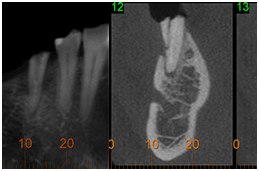

• Visualizar tamanho, forma e número de canais radiculares

Endodontia (obliteração radicular no 11)